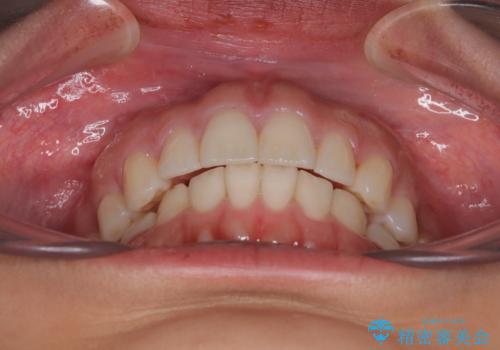

【モニター】突出した前歯 補助装置を併用したインビザライン矯正

- 上下前歯が非接触となり、前方に突出していることを気にして来院された患者様です。

咬合力が強く、全体的に歯がすり減っているため、インビザライン単独での上顎歯列移動は困難と判断し、補助装置により上顎歯列を後方移動させ、その後インビザラインにて仕上げていくこととしました。

補助装置なしでも改善できる可能性はありましたが、補助装置で確実性を上げ、短期間できっちりと仕上げることができました。